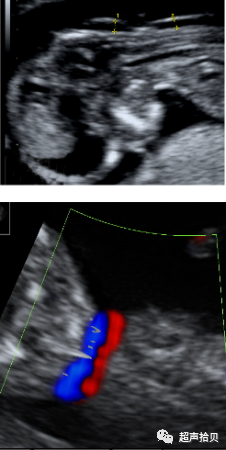

胎儿心率

• 测量胎儿心率 (FHR):

获得胎儿心脏横切面或长轴切面

在胎儿静息期使用脉冲多普勒获取6-10个心脏周期

使用超声波仪自带软件计算胎儿心率

正常妊娠,胎儿心率自第5孕周开始从110次/分增加到第10孕周的170次/分,然后逐渐降低,到第14孕周时降低到150次/分.